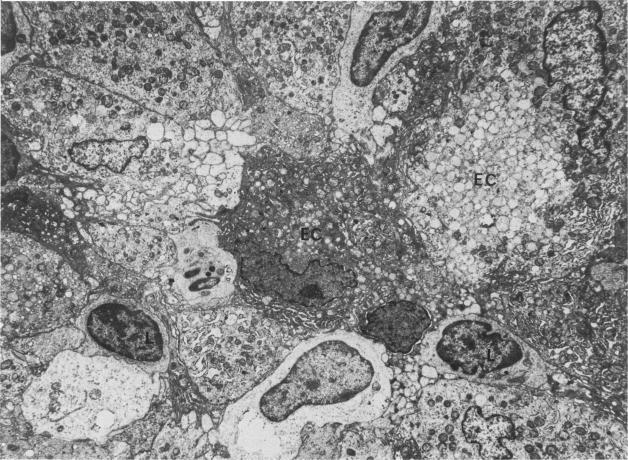

The authors undertook this study to determine whether there were any morphologic changes in bronchoalveolar lavage lymphocytes and macrophages in sarcoidosis and, in particular, to determine whether changes described previously in the mononuclear phagocytes of sarcoid granulomas were also evident in such cells obtained by lavage. Lavage cells from 28 sarcoidosis patients were studied by transmission electron microscopy and compared with lavage cells from 17 control subjects and with lung tissue granulomas from 5 sarcoidosis patients. Interactions between mononuclear phagocytes, especially subplasmalemmal linear densities, and between these cells and lymphocytes were observed in both the tissue granulomas and lavage specimens from sarcoidosis patients. Subplasmalemmal linear densities were never observed in control lavage specimens. Fully developed epitheloid cells were not identified in lavage specimens, but differences were nevertheless found between the lavage cells from sarcoidosis patients and control subjects: in particular, alveolar macrophages in sarcoidosis were larger and showed better developed pseudopodia, more marked polarity, less nuclear heterochromatin, and lysosomes that were larger and more numerous but less electron-dense than normal. Lymphocytes were also enlarged and contained more lysosomes. It is concluded that although there are only a few similarities between the cells of the granuloma and those obtained by bronchoalveolar lavage in sarcoidosis, there are noticeable differences between the lavage cells of sarcoidosis patients and control subjects. In sarcoidosis, a variable proportion (10-70%) of the lavage cells show morphologic features of "activation."

作者开展这项研究,旨在确定结节病患者支气管肺泡灌洗中的淋巴细胞和巨噬细胞是否存在形态学变化,尤其是确定先前在结节病肉芽肿单核吞噬细胞中所描述的变化,在通过灌洗获取的此类细胞中是否也很明显。通过透射电子显微镜对28例结节病患者的灌洗细胞进行研究,并与17例对照受试者的灌洗细胞以及5例结节病患者的肺组织肉芽肿进行比较。在结节病患者的组织肉芽肿和灌洗标本中均观察到单核吞噬细胞之间的相互作用,尤其是质膜下线性致密物,以及这些细胞与淋巴细胞之间的相互作用。在对照灌洗标本中从未观察到质膜下线性致密物。在灌洗标本中未识别出完全发育的上皮样细胞,但结节病患者的灌洗细胞与对照受试者的灌洗细胞之间仍存在差异:特别是,结节病中的肺泡巨噬细胞更大,伪足更发达,极性更明显,核异染色质更少,溶酶体更大且数量更多,但电子密度低于正常水平。淋巴细胞也增大,且含有更多溶酶体。得出的结论是,尽管结节病肉芽肿细胞与通过支气管肺泡灌洗获得的细胞之间只有少数相似之处,但结节病患者的灌洗细胞与对照受试者的灌洗细胞之间存在明显差异。在结节病中,可变比例(10 - 70%)的灌洗细胞呈现出“激活”的形态学特征。